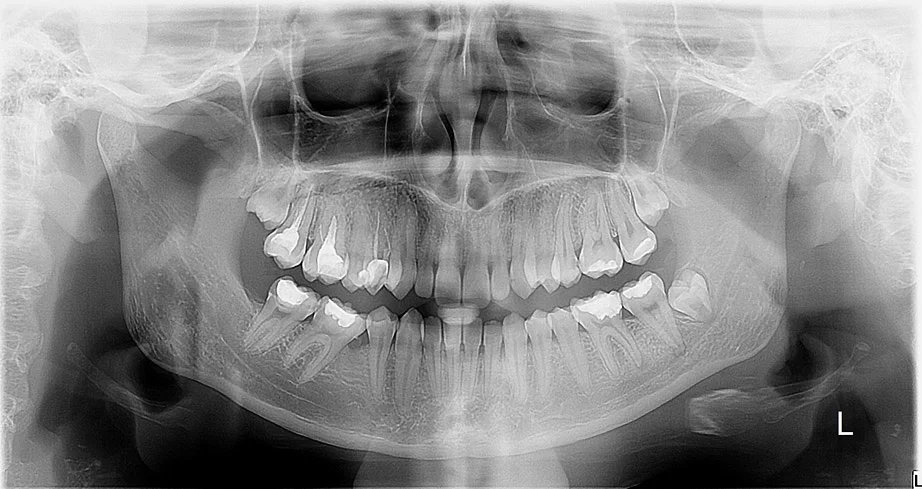

Ortopan Zadar – panoramska snimka zubi

Ortopan (panoramski RTG) – brzo i sigurno snimanje u Zadru

Panoramska RTG snimka (ortopan) prikazuje sve zube, čeljusti, sinuse i okolne strukture na jednoj slici.

U Apex Dental centru koristimo jedan od najboljih uređaja ikad napravljenih za slikanje digitalnog ortopana Soredex Cranex 3d čiji je senzor posebno dobro optimiziran baš za ovu vrstu slike s minimalnom dozom zračenja te s velikom sigurnošću i iznimnim ponosom možemo mirne duše tvrditi da naš ortopan spada u red najboljih na tržištu s iznimno visokom jasnoćom slike.

Zašto se radi ortopan?

• Prvi pregled kompletnog stanja zuba. Kad krećete sređivati zube poželjno je na prvi pregled doći sa ortopanom da Vaš stomatolog ima cjeloviti uvid u stanje vaših zubi i čeljusti.

• Analiza karijesa, upala, cista i kanala

• Planiranje protetske terapije

• Kontrola zubi prije vađenja.

• Slika za oralnu kirurgiju ukoliko vas Vaš stomatolog šalje vaditi zaostali zubni korjen ili impaktirane umnjake kod specijalista oralne kirurgije

• Kontrola nicanja kod djece i odraslih. U prijelaznom razdoblju odnosno izmjeni mliječne i trajne denticije iznimno je važno znati u kojoj je fazi izmjena zubi da se pravovremeno može reagirati vađenjem mliječnih zubi ukoliko je trajni zub već trebao izaći.

Snimanje traje manje od 10 sekundi, a snimka je odmah dostupna u digitalnom obliku kao i printanom na filmu te na cd-u.

Ortopan je najčešća rtg snimka u današnjoj dentalnoj medicini.

Svaki temeljiti doktor dentalne medicine zatražiti će već na prvom pregledu da snimite ortopan kako bi mogao precizno utvrditi početno stanje,dijagnosticirati probleme i planirati terapiju

Koliko je zračenja u jednom ortopanu?

• Efektivna doza zračenja: Tipično se kreće između 5,5 i 22 mikro-Sieverta (µSv), što odgovara otprilike 1–5 dana prirodnog pozadinskog zračenja(dakle najnormalnijeg boravka na otvorenom).

• U poređenju sa drugim rendgenskim snimcima:

• Bitewing (mali rendgenski snimak): oko 0,005 mSv (1 dan pozadinskog zračenja).

• CT skener: oko 2 mSv (1 godina pozadinskog zračenja).

Praktične informacije

• Trajanje procedure: Snimanje traje oko 12–20 sekundi, tokom kojih se X-ray aparat rotira oko glave pacijenta.

• Zaštita pacijenta: Obično se koristi olovni prsluk kako bi se dodatno smanjila izloženost zračenju.

• Sigurnost: Zračenje u ortopanu je mnogo niže nego kod CT skenera ili medicinskih rendgenskih snimaka, poput rendgena grudnog koša, koji ima dozu od 0,02 mSv.

Zaključak

Ortopan pruža detaljan pregled dentalnih i maksilofacijalnih struktura uz minimalnu izloženost zračenju. Efektivna doza je niska i ne predstavlja značajan rizik za zdravlje.